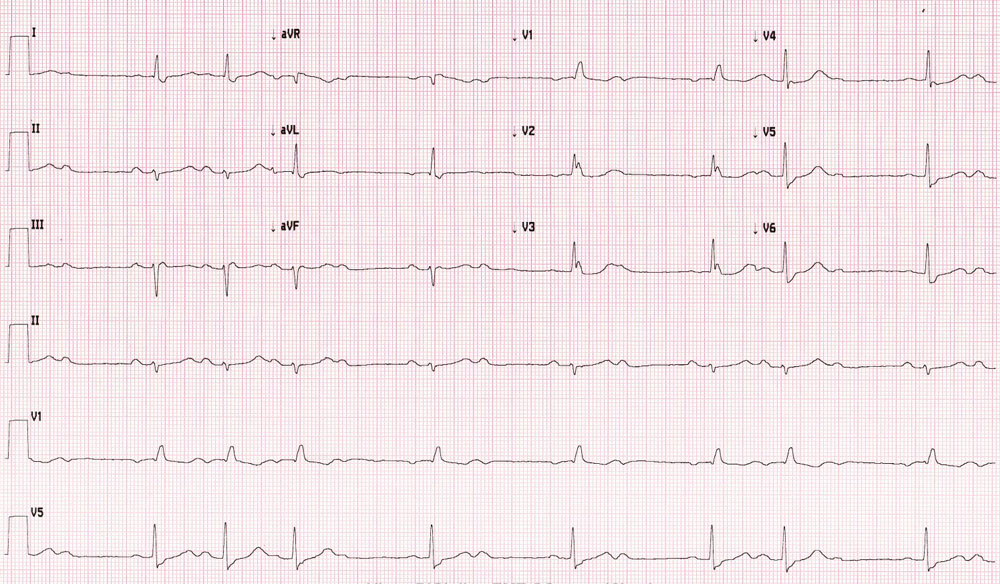

Osnovna funkcija pejsmejkera je korekcija sporog ritma srca ili zastoja u srčanom radu (usled nedovoljnih električnih impulsa ili njihovog potunog izostanka/zastoja). Ovi pejsmejkeri se zovu antibradikardni pejsmejkeri.

Simptomi koji se javljaju usled ove poremećene funkcije ritma srca su nesvestica i vrtoglavica prilikom hoda po ravnom, kao i potpuni gubitak svesti. Pacijent može osećati i samo zamor pri uobičajenim fizičkim aktivnostima ukoliko broj otkucaja srca ne može zadovoljavajuće da se poveća. Zastoj u radu srca izaziva gubitak svesti ukoliko traje dovoljno dugo da izostane potrebna ishrana mozga. Tom prilikom pacijenti se često povređuju.